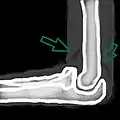

Skyline view of the patella demonstrating a large joint effusion as marked by the arrow.